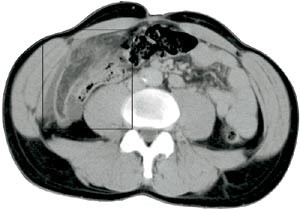

Pasient 1. En 56 år gammel mann med medikamentelt behandlet hypertensjon og tidligere operert brokk i epigastriet ble henvist fra primærlege til ultralydundersøkelse av abdomen på grunn av smerter under venstre costalbue, tiltakende over en uke og konstante de siste tre dager. Undersøkelsen viste en ekkorik, hovedsakelig homogen, 12 x 3 cm stor oval masse med enkelte lavekkogene avsnitt i sentrale deler og et tynt hypoekkoisk sjikt omkring (fig 1). Supplerende CT viste en 10 x 3 cm stor oppfylling i det tilsvarende området under venstre costalbue. Den lå tett an mot bukveggen foran ventrikkelen og hadde attenuasjon som fettvev med ødem (fig 2). Klinisk var han subfebril, direkte og indirekte øm medialt og nedenfor venstre costalbue, samt hadde forverring av smerten ved hoste. Man mistenkte omentnekrose, og pasienten ble operert ved laparoskopi. Alt nekrotisk vev ble resecert, og histologisk diagnose var fettvev med akutt hemoragisk infarkt og subserøs fibrose. Postoperativt forløp var ukomplisert.

Intraabdominalt fokalt fettinfarkt fremstilles ved CT som en velavgrenset oppfylling med fettattenuasjon av noe høyere tetthet enn normalt peritonealt fettvev (ca. -60 Hounsfield-enheter versus -120 Hounsfield-enheter) (1, 2, 6) – (9). I fettoppfyllingen ses høyattenuerende linjer eller drag arrangert i konsentrisk eller spiralaktig mønster (oftest kalt «stranding») og eventuelt mer veldefinerte foci med høyere tetthet. Dette indikerer ødem og blødning. En liten mengde fri væske nær lesjonen er hyppig til stede. Som ved ultrasonografi kan man finne fortykkelse av tarmvegg og peritoneum og masseeffekt.

Hyperattenuerende perifert sjikt omkring lesjonen er også beskrevet, men da oppfattet som å være indikator for at epiploisk appendagitt foreligger (5, 8). Vår andre pasient med omentinfarkt fremviste delvis dette tegnet på CT (fig 4), men hos ham brukte man intravenøs kontrast, som kan ha gitt oppladning i inflammert peritoneum. Andre kriterier som kan gi mulighet for å skille mellom disse to entiteter, er størrelsen og relasjonen til colon. Infarkt av oment er større enn epiploisk appendagitt, og omentinfarkt befinner seg medialt for colon ascendens eller descendens, mens epiploisk appendagitt ligger anteriørt eller anterolateralt (8). Massen ved omentinfarkt er heterogen og oftest til høyre i abdomen, mens epiploisk appendagitt er mer homogen og hyppigst på venstre side (1, 8). I praksis har det liten betydning å skille disse to former for fettinfarkt, fordi det ikke foreligger overbevisende diskriminerende kriterier og fordi symptomatologi og behandling er lik. Det samme gjelder enten det foreligger torsjon av omentet eller primært infarkt (5).